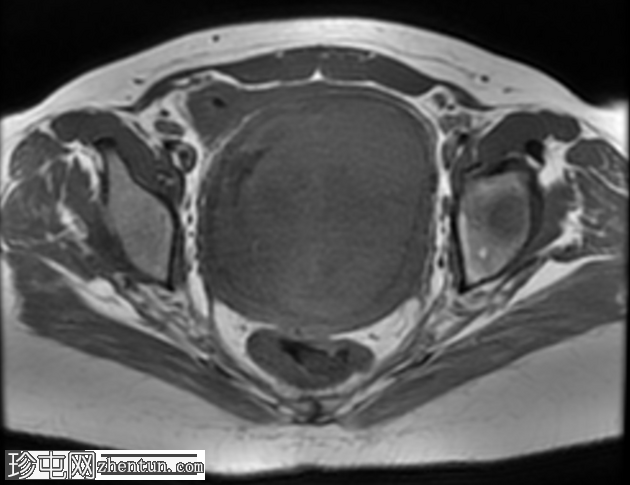

轴位T2

脂肪饱和度

宫颈后壁及子宫下段中心可见一约11.5 × 10 × 10厘米的不规则局灶性病变。该病变在T1脂肪饱和图像上呈等信号,伴有一偏心低信号区,中心有一细微高信号,提示有出血。

在T2加权图像上,病变呈中高信号,伴有囊性变性区域,以及与T1暗区相对应的偏心T2暗信号,也与含铁血黄素相符。

病变显示弥散受限区域,DWI信号强度高(等于或高于子宫内膜),实体强化区域ADC映射信号低,测量值小于0.9×10⁻³ mm²/秒(约0.755×10⁻³ mm²/秒)。

注射造影剂后,病变实体部分呈现均匀强化。

肿块对邻近结构产生显著的占位效应,向前压迫膀胱。膀胱呈空虚状态,Foley导尿管位于原位。

印象:放射学特征高度提示平滑肌肉瘤;有必要进一步评估